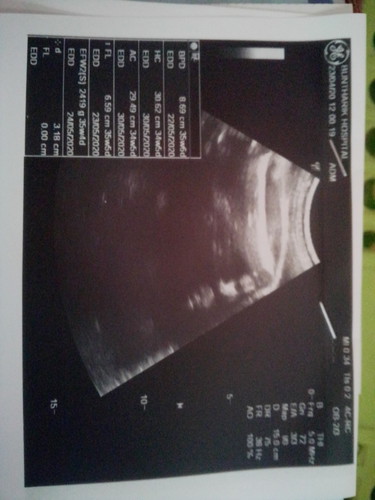

35+3 ค่ะหมอนัดไปอัลตร้าซาวด์แต่หมอไม่บอกเพศต้องดูตรงไหนค่ะถึงจะทราบเพศ